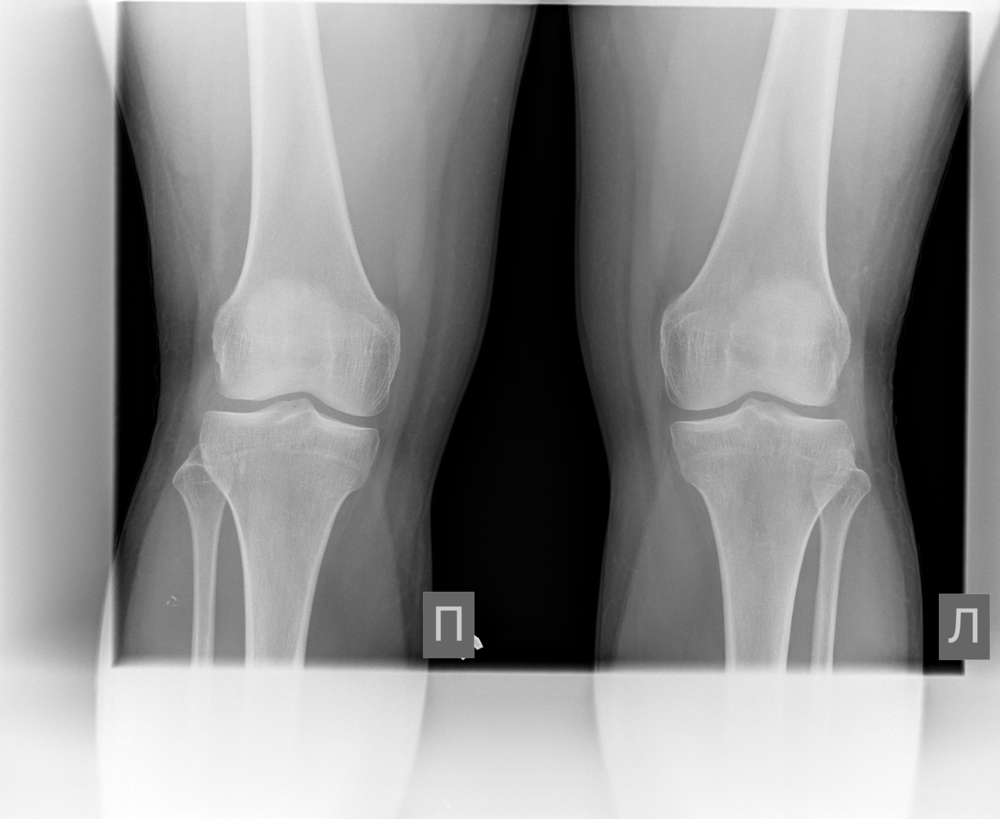

ИИ и алгоритмы интеллектуального анализа для рентгена коленного сустава. Оцените дегенеративные процессы менее чем за 1 минуту